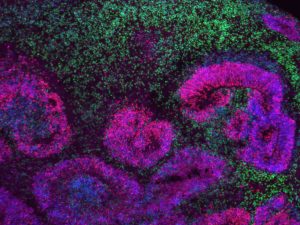

El-mayor-mapa-del-cerebro-en-desarrollo-revela-las-fases-en-las-que-se-originan-los-trastornos-neurologicos